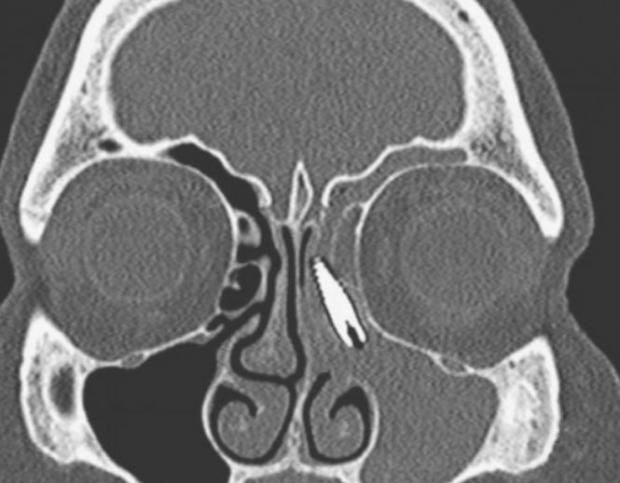

O femeie din Italia s-a dus la spital după doi ani în care a avut dureri puternice în nas.

Doctorii au descoperit că pensionara avea în nas un șurub care îi fusese montat în maxilar în urmă cu mulți ani.

Șurubul de doi centimentri s-a deplasat de la locul inițial și a ajuns în nas.

Femeia a fost operată și și-a revenit complet în scurt timp.